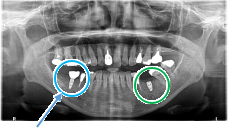

Before

青丸の部分を削り取りました